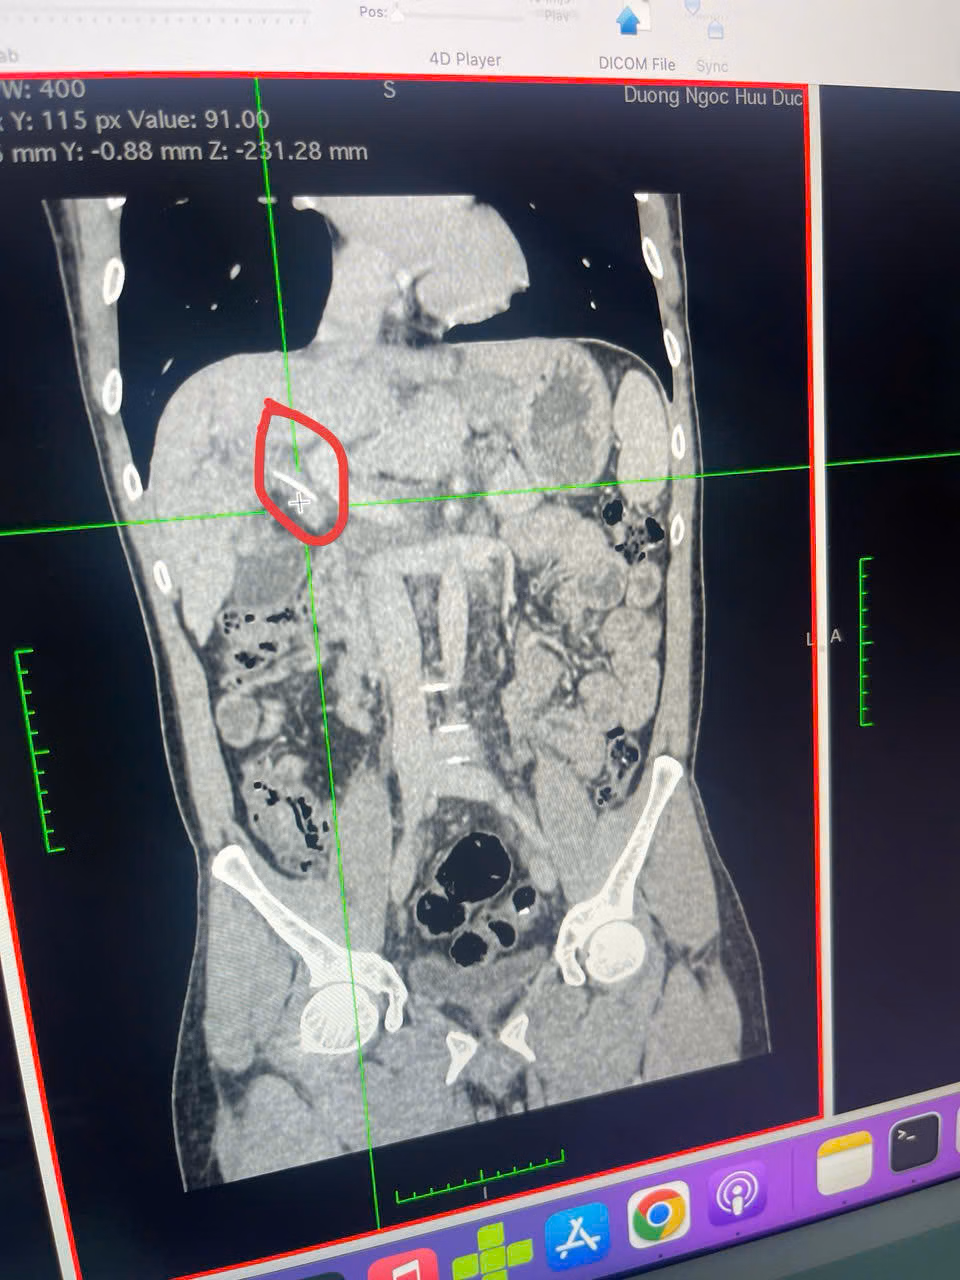

Kết quả chụp cắt lớp vi tính phát hiện một dị vật cản quang dài gần 3cm nghi nằm trong đường mật, gây tắc nghẽn. Sau khi hội chẩn liên chuyên khoa, ê-kíp quyết định thực hiện nội soi mật tụy ngược dòng (ERCP) để can thiệp.

Trong quá trình nội soi, bác sĩ phát hiện xương cá đâm xuyên vào ống gan chung, phía trên hình thành sỏi kẹt quanh dị vật. Dưới sự hỗ trợ của hệ thống nội soi Spyglass, các bác sĩ đã gắp thành công chiếc xương cá, đồng thời đặt stent để giải phóng tắc nghẽn đường mật. Sau gần 2 giờ can thiệp, bệnh nhân ổn định, giảm đau rõ rệt, tình trạng vàng da cải thiện và dự kiến xuất viện trong vài ngày tới.